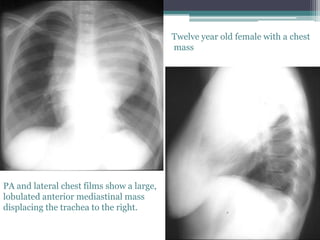

PA and lateral chest films show a large,

lobulated anterior mediastinal mass

displacing the trachea to the right.

Twelve year old female with a chest

mass

A chest CT exam shows the mass to extend from the neck to the diaphragm,

compressing the tracheal and left mainstem bronchus leading to left lower

lobe atelectasis. The chest wall mass is partially eroding the sternum and

there is periosteal reaction. Axillary adenopathy is present also.

Dx:Lymphoma, Hodgkin, Anterior Mediastinal, Sternal Involvement